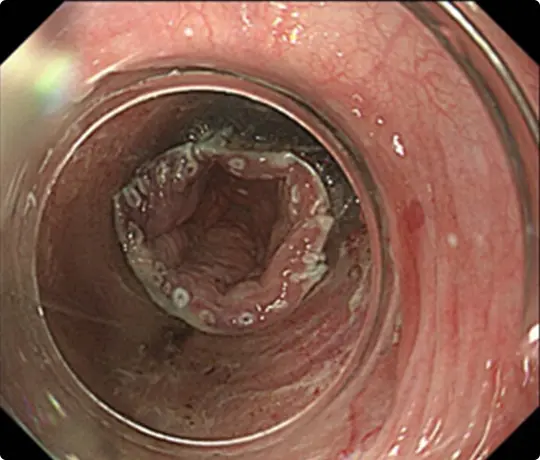

全周性の食道がんに対するESDです。

がんの範囲を分かりやすくするため、食道にヨード染色を行っています。ピンク色に見えるところに食道がんがあります(食道の全周を占めています)。

病変の周りに目印のため、電気メスで白いマークを付けています。

粘膜の下に液体を注入して病変を浮かせます。

病変の外側を電気メスで切開したところ。

粘膜の下の組織(粘膜下層)を電気メスで剥がしているところです。

全周性のESD後です。穿孔(壁に穴があくこと)などの問題なく、病変を切除しました。切除後は潰瘍が出来ますが、1~2ヵ月で治ります。

食道は元々細いため、大きな病変を切除した後は、潰瘍の治癒に伴い食道がより細くなり、ご飯が通らなくなる場合があります。近年、ステロイドの注射で細くなるのを予防出来ることが分かって来ました。

当科でも広範な食道ESD後はステロイドを注射し、食道が細くなるのを予防しています。